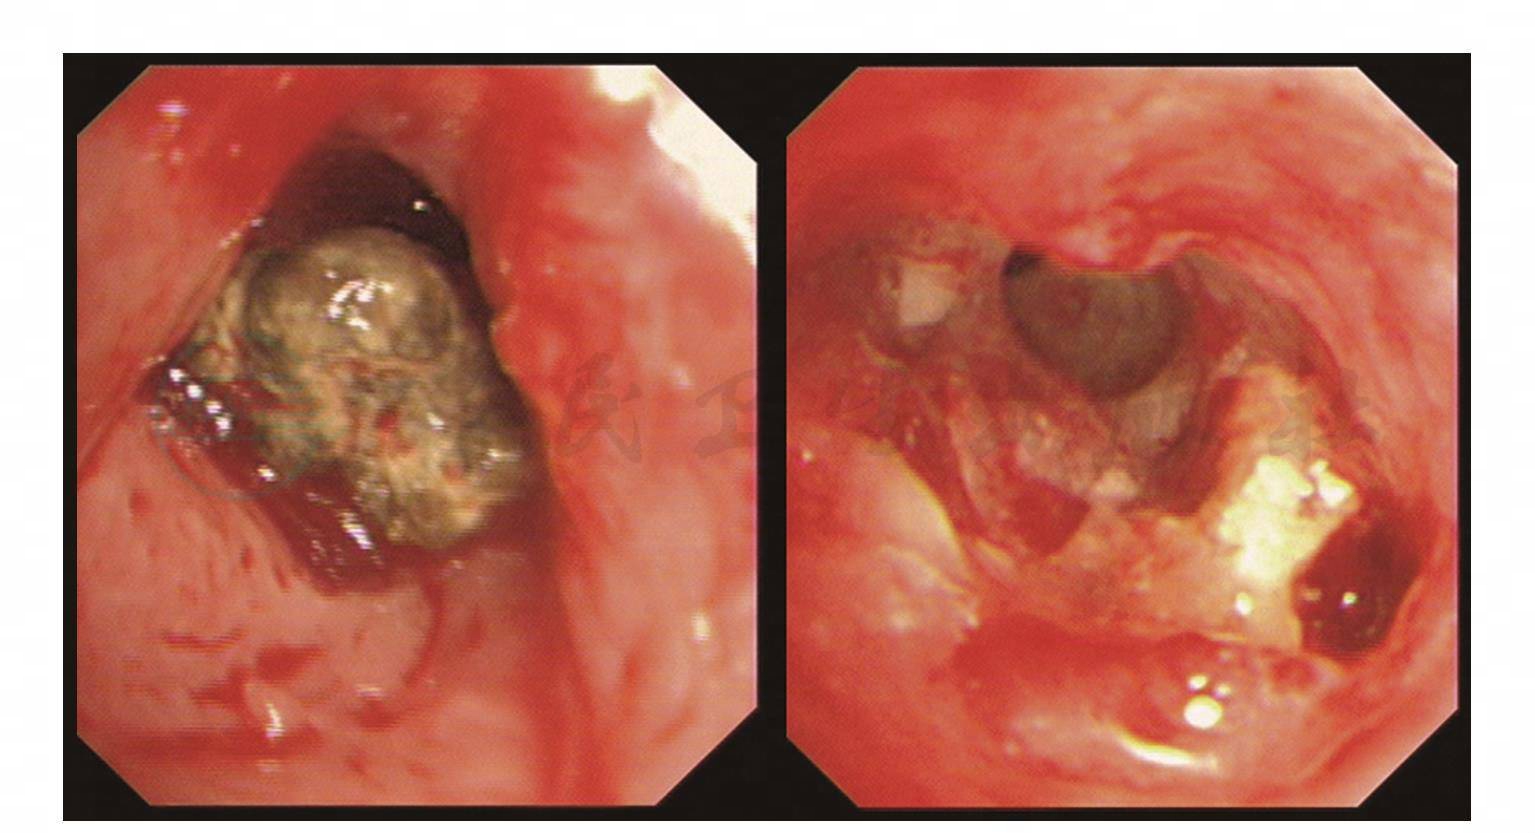

支气管镜检查:可弯曲支气管镜是诊断支气管结石最直接、最重要的手段,一般观察到支气管腔内结石即可确诊。但对有些支气管腔内结石由于反复炎症后被肉芽组织包裹时,容易误诊为肿瘤等疾病,此时可行活检,待病理排除肿瘤后再将肉芽清理,暴露结石,明确诊断(彩图3)。

图3 气管支气管结石病支气管镜下表现

注:支气管腔内见灰黑色类圆形物,质硬,以及取出后管壁的情况。